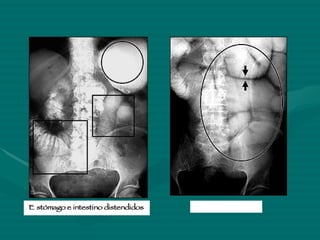

Íleo

Obstrucción del intestino delgado vólvulus

RADIOGRAFÍA SIMPLE DE ABDOMEN Hemos de evaluar la presencia de diversas anormalidades: Alteraciones del Patrón aéreo Aire  intraluminal Aire  extraluminal Íleo mecánico Íleo paralítico Abscesos Perforación libre Presencia de gas Masas  abdominales Calcificaciones

RADIOLOGIA Aunque no están estandarizadas, típicamente se realizan tres proyecciones abdominales:   *Decúbito supino.   *Bipedestación ( niveles hidroaéreos: Neumoperitoneo)  *Decúbitos laterales. Radiografía de abdomen simple de pie e xaminar rutinariamente:  Sombras de los Psoas.  Patrón aéreo intestinal.  Aire ectópico.  Líquido libre intraperitoneal. Abdomen Ag:  Util el uso de Contraste (sulfato de Bario) Contrastes hidrosolubles Yodado: Diferenciacion de Ileo mecanico con el Adinamico Enema Opaco de Colon:  Invaginacion Intestinal, Sospecha de Volvulo, Obstruccion intestinal.